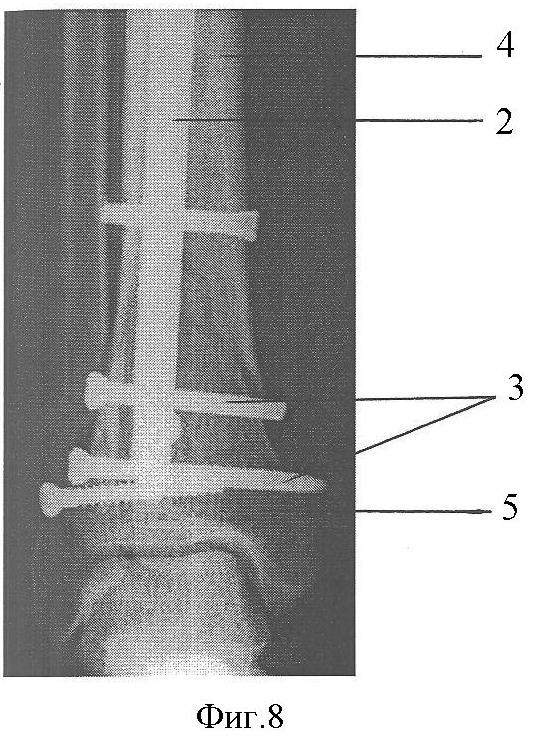

Фиг.8. Постоперационная рентгенограмма в прямой проекции.

Клинический пример: Пациентка А., 43 лет. Диагноз: Закрытый перелом дистальных метафизов обеих костей правой голени (фиг.4, 5). Произведена операция (фиг.8, 9), при этом после внедрения стержня 2 интрамедуллярно под контролем электронно-оптического преобразователя проведены репозиционно-блокирующие винты 3 через костные отломки 4, 5 и резьбовые отверстия 1 в стержне 2, при установке винтов 3 (фиг.3, 6, 7) достигнута компрессия отломков 4, 5 с устранением остаточных их смещений за счет притягивания отломков 4, 5 к стержню 2 головками винтов 3 и достигнута окончательная репозиция и полиаксиальная жесткая стабилизация отломков 4, 5, исключающих возможность смещений отломков 4,5 после установки металлоконструкции и в послеоперационном периоде. Винты 3 выполнили как репонирующую, так и блокирующую роль. Полная нагрузка на ногу после операции (фиг.10). Срок нетрудоспособности 4 недели.